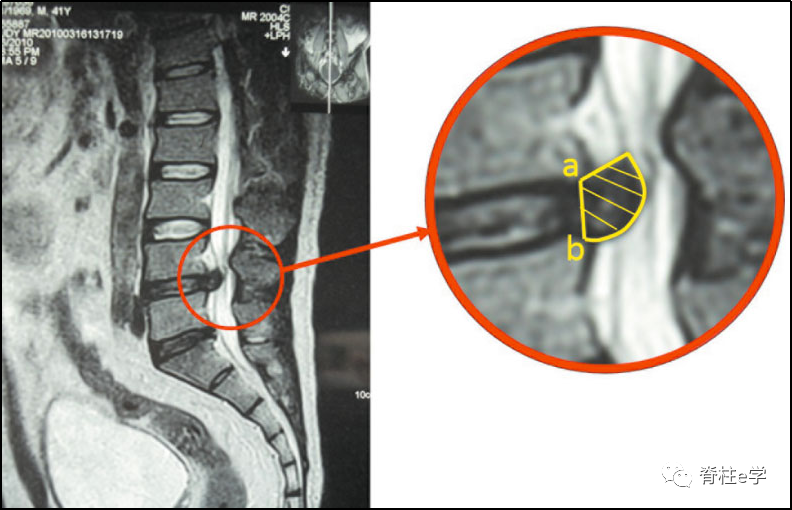

MRI对软组织分辨率较高,能清晰显示突出髓核组织的形态、位置、信号特点及神经继发性改变,并可获得多层面、多角度图像。基于MRI显示的椎间盘突出程度预测腰椎间盘突出后重吸收,具有重要意义。目前,由于大部分对突出物体积变化的研究还停留于肉眼对MRI影像的直观感觉,为了精确反映突出物体积的变化。本文推荐国内学者俞鹏飞首创的基于MRI测定腰椎间盘突出物体积及其突出率和吸收率的计算方法:

a:上椎体后缘中点至椎管后壁的长度(椎管直径);

b:从突出物最高点到椎管后壁的距离;

突出率 = [(a-b)/a ] X 100%

在MRI矢状位T2W1图像上,以上位椎体后下缘及下位椎体后上缘连线为内边界,突出物边缘作为外边界,计算突出物体积。

突出物体积 =(层间距 + 层厚)X∑每一层突出物面积,

吸收率 =(治疗前突出物体积-治疗后突出物体积) /治疗前突出物体积X100%